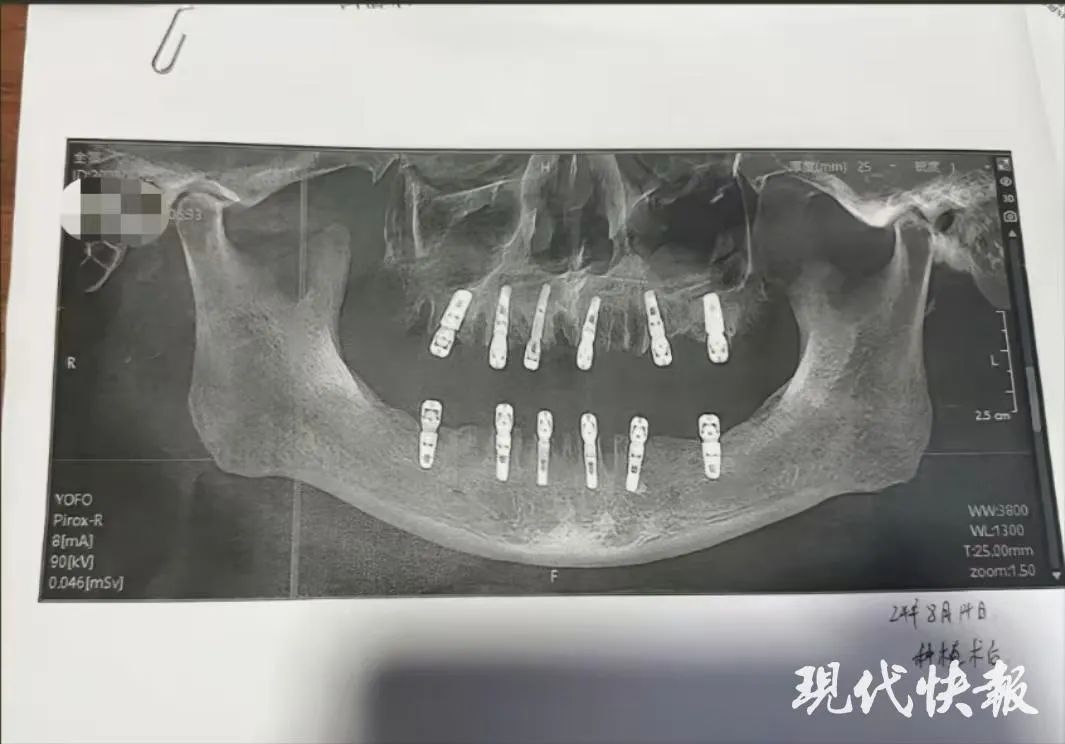

舒女士的父亲黄某8月14日在德维口腔医院接受牙科手术。根据种植手术同意书显示,本次治疗拔牙23颗、种植牙齿12颗,并且均为即刻修复,即“当天拔、当天种”,负责进行治疗的医师为袁某。

然而,据黄某的种植手术同意书,在其接受的手术中,有多颗臼齿在拔除当天就进行了种植,与工作人员所介绍的不符。